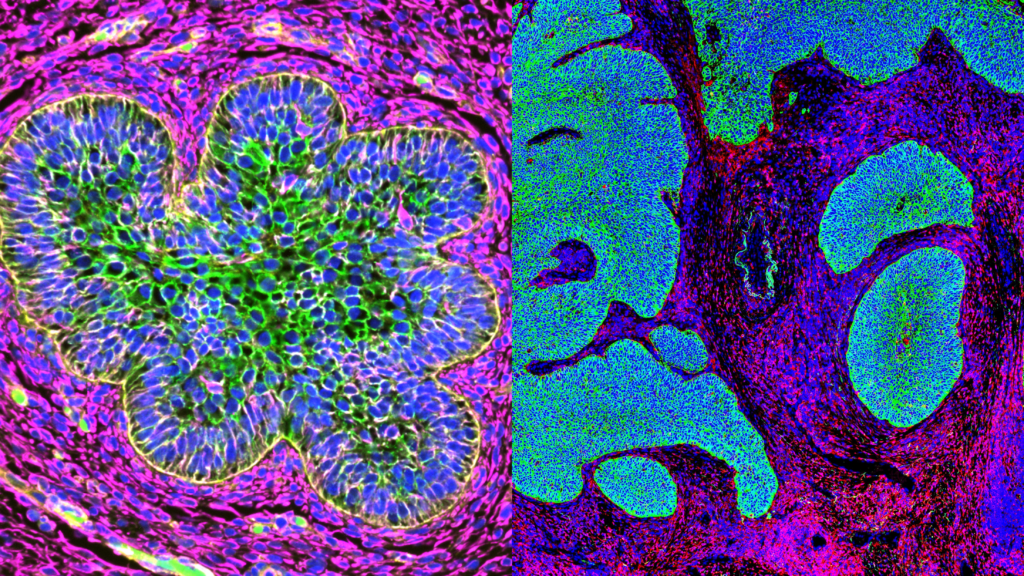

Laetitia Lecante from University of Aberdeen will present her work on sex-dimorphism in the prenatal mammary bud transcriptome. Using GeoMx, she generated new data on the regulation of sex-specific development of the human prenatal mammary bud.

| 8:35AM PST | 4:35PM BST | Blossoming Beginnings: The Delicate Beauty of Mammary Buds, Laetitia Lecante, University of Aberdeen |